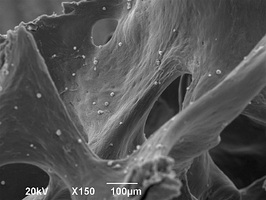

Биоимплантаты аллогенные стерильные губчатые механически и и ультразвуком обработанные.

По внешнему виду представляет собой пористый губчатый блок номинального размера.

2. Поверхность и структура материала для изготовления биоимплантатов